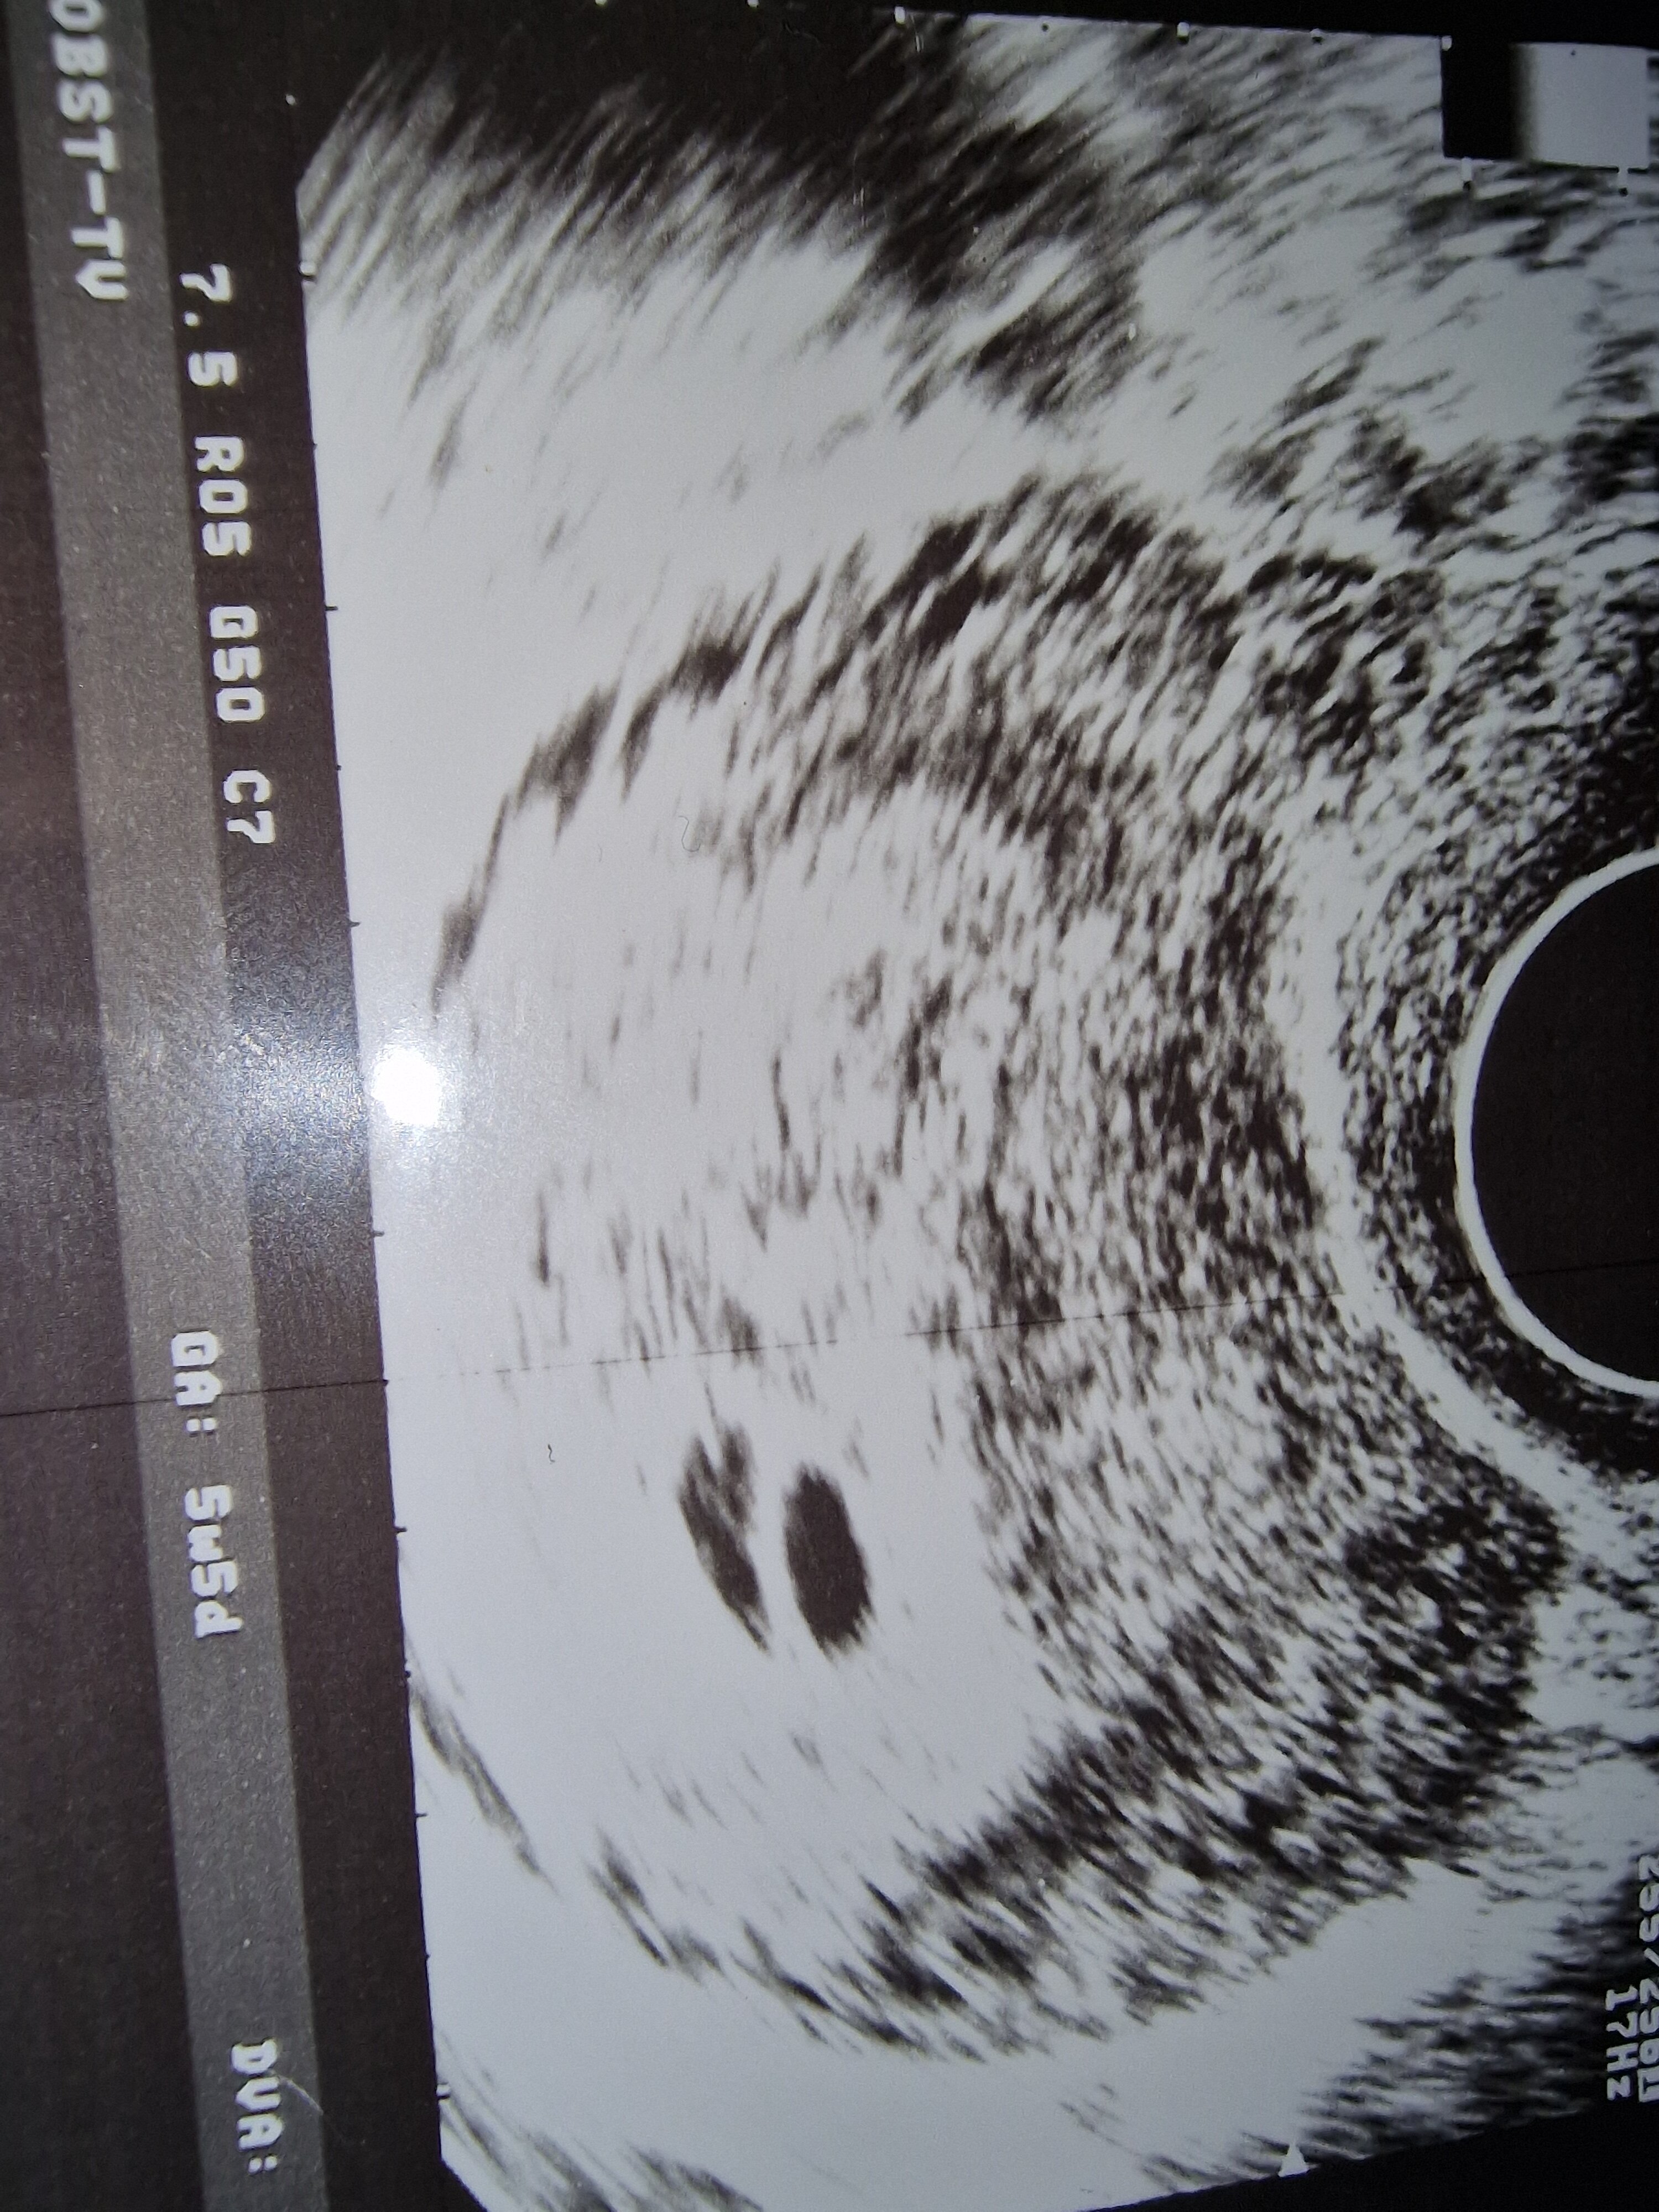

Hej czy myślicie , że to bliźniaki?

Jeśli tak to dlaczego jeden pęcherzyk jest większy od drugiego?

Oznacza to, że jesteś w mniej więcej 6 tygodniu ciąży i jest pęcherzyk (lub 2?) w macicy.